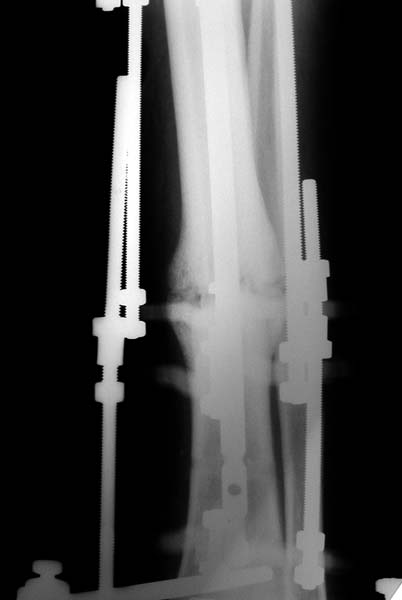

No hollow reamers and nails are still availble yet, so UTN 10 mm was used. After perQ osteotomy of the fibula i tried to open the canal, and the awl was passed to the distal fragment only after closed mobilization of the site to make some antecurvation. It resulted with some anterior translation of the distal fragment :( After impaction the nail was locked dynamically. Images attached. Comments/critics are welcome.

Today the case was criticized at the week clinical report for the antecurvation deformity... Un our vice-director tries to prove that such a malalignment is of great clinical importance.

I would expect the deformity of the case of nailed tibia shaft nonunion (slight apex posterior and slight posterior translation) to be of no definite and small theoretical clinical importance.